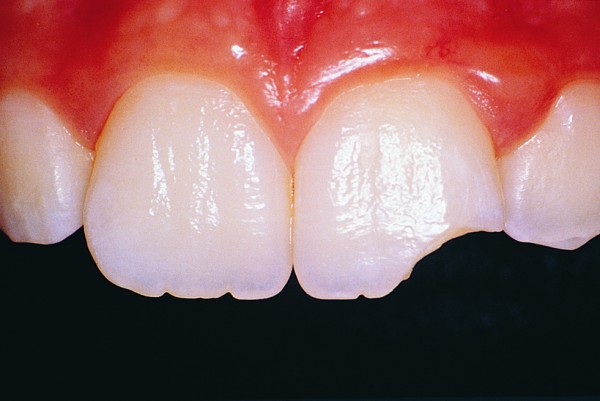

Povrede tvrdih zubnih tkiva se manifestuju kao:

- Naprsnuće gleđi

- Prelomi zuba

- I klasa – prelom gleđi

- II klasa – prelom gleđi i dentina

U slučajevima I i II klase preloma zuba terapija podrazumeva nadogradnju krunice estetskim materijalima već u prvoj poseti stomatologu.